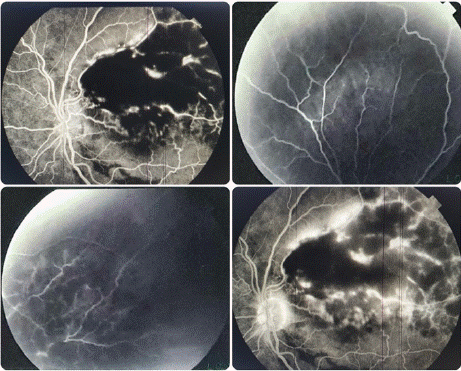

Autofluoroscence imaging revealed multiple hyperautofluorescent lesions (44 of the hemorrhagic zone) corresponding to the flecks. Fluorescein angiography of the LE showed hypofluorescence caused by decreased transmission due to the presence of hemorrhage and superior hyperfluorescence with leakage possibly indicating neovascularization. In the RE, hyperfluorescence focally at the fleck sites corresponded to pigment epithelial changes (Figure 3).

Figure 3: Fluorescein angiography of the LE.